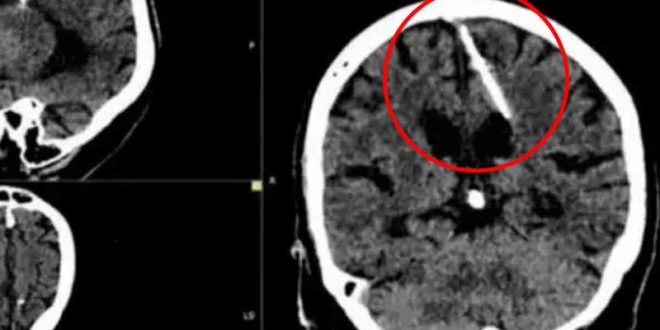

Lo que era un chequeo médico rutinario se convirtió en una pesadilla luego de que especialistas hallaron una aguja de 3 centímetros de largo en el cerebro de una mujer de 80 años en Rusia.

Aunque no se han revelado detalles del lugar exacto en donde ocurrió este suceso, o la fecha en la que se registró, autoridades sanitarias dijeron que la aguja se encontraba en el lóbulo parietal izquierdo de la mujer anónima quien al parecer la tuvo alojada en el cerebro desde que era una bebé y nunca le provocó molestias ni dolores de cabeza.

En tanto, los médicos detallaron que el objeto estuvo alojado en su cerebro desde su nacimiento y explicaron que es probable que sus padres hayan trataron de matarla en su infancia, una práctica muy recurrida en tiempos de guerra y hambruna.

Durante la Segunda Guerra Mundial los padres desesperados introducían una aguja en un punto blando de la cabeza del recién nacido, conocido como la fontanela, donde los huesos del cráneo aún no se habían fusionado, el punto se cierra y oculta la aguja, y el bebé moría.

Los médicos decidieron no retirar el objeto del cebero de la mujer, ya que no representa un peligro para ella y ha vivido sin problemas de salud durante toda su vida, por lo que someterla a una cirugía podría ser riesgoso por su edad y podría ser grave para ella. Información Excelsior.com.mx